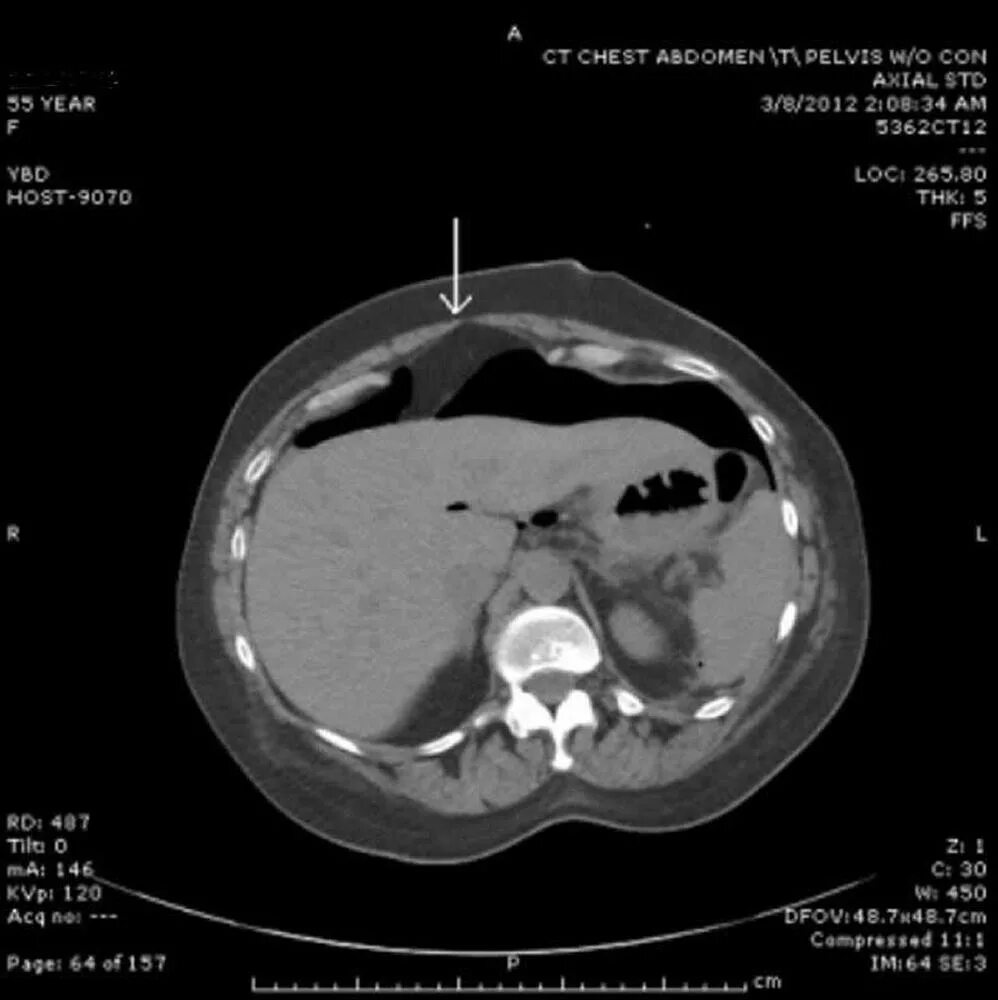

Язва желудка кт